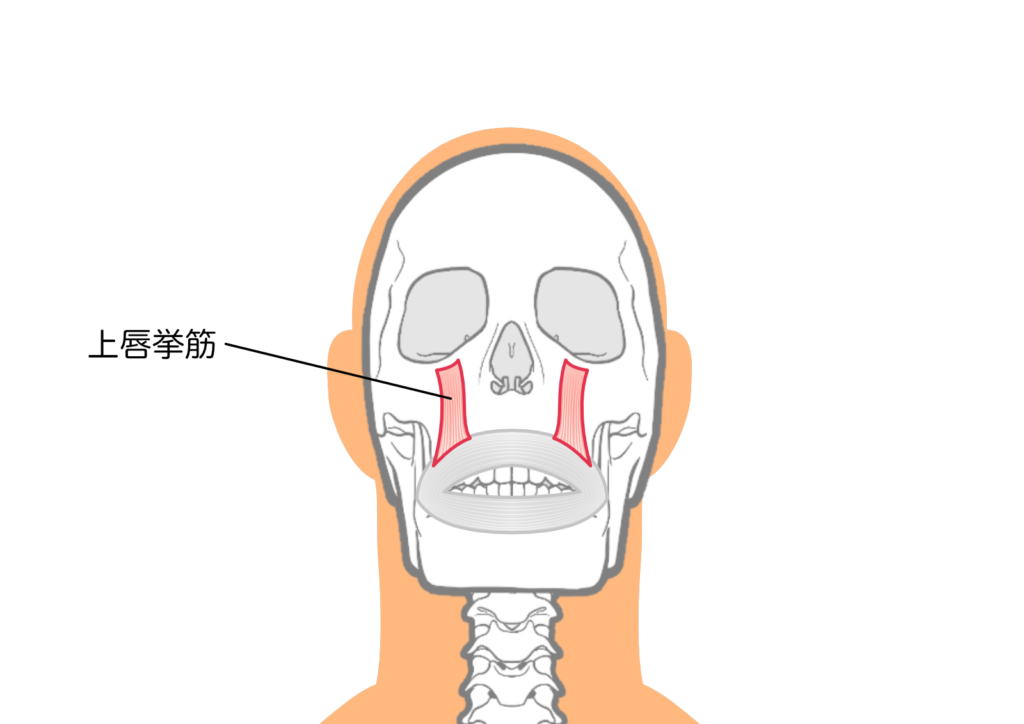

難しいタイプ③表情筋の働きが強いタイプ

上唇を持ち上げる筋肉(上唇挙上筋)の働きが強すぎると、笑ったときに上唇が過剰に引き上げられ、歯ぐきが大きく露出してしまいます。

この場合、矯正治療だけでは十分な改善が得られないことがあります。

そのため、矯正治療と並行してボトックス注射などで筋肉の働きを抑える補助的な治療を組み合わせることで、より自然な笑顔に近づけることができます。

Q5. ボトックス注射との併用は可能ですか?

A. 可能です。上唇を持ち上げる筋肉の働きが強い方には、インビザライン治療と並行してボトックス注射を行うことで、より効果的な改善が期待できることがあります。

ただし、ボトックスの効果は3〜6か月程度のため、矯正治療で根本的な改善を図ることが重要です。